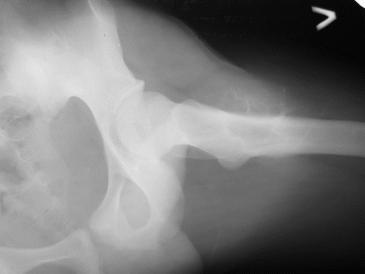

Обратился парень 15ти лет с жалобами на боли в левом коленном суставе. При обследовании обнаружена опухоль в в/з левой бедренной кости.

Проведено КТ заключение( остеохондрома) Подскажите пожалуйста, стоит ли сделать биопсию перед операцией .Кокой операционный доступ и технику операции Вы посоветуете.